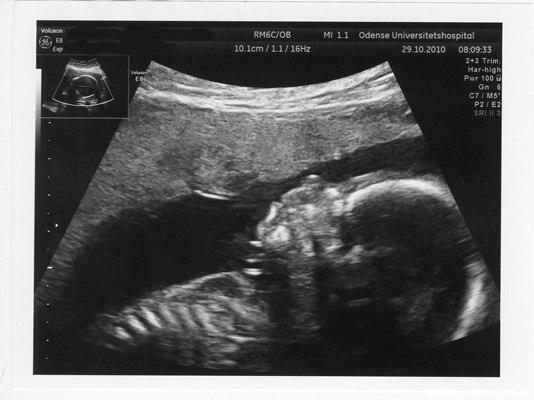

Men det var ellers en noget livlig unge jeg har tumlende rundt derinde, den vendte og drejede sig i et væk, og hun mente at påtrods af at min moderkage ligger foran så kan det ikke vare længe før jeg kan mærke den lille vildbasse. Hun var meget tilfreds og sagde at den trives godt, vokser som den skal og alt så ud til at være hvor det skulle være og der var alle fingre og tæer.

Men desværre kunne hun ikke se kønnet sagde hun, for hver gang hun var lige ved og næsten kunne se det så vendte den lille røver sig om så vi kun kunne se en røv eller ryggen. Nå sagde jeg så, jamen så skulle vi nok bare ikke vide det, så er det bare en hemmelighed. Så skulle hun til at pakke væk, men.... så tog hun lige scanneren på igen - ej jeg kigger lige en gang mere sagde hun... uh sagde jeg tror måske at hvis jeg umiddelbart skal give et bud så skal i have en lille pige.

Nå det blev langt, men i skal da også lige have et par billeder af vidunderet uanset om det er en lille pige eller en lille dreng.